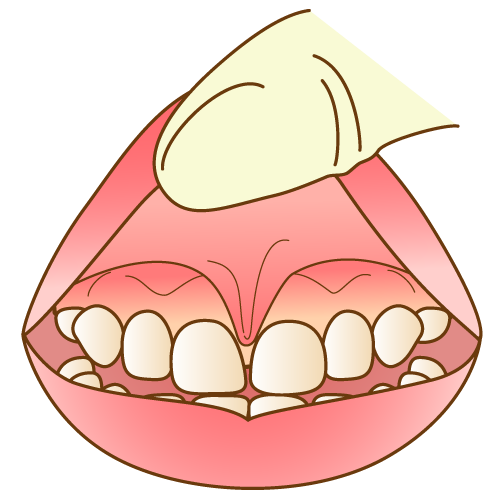

小帯異常

上唇小帯異常

○上唇小帯が肥大し、口唇への移行部で扇状に広がる。

○上唇小帯の付着部位が歯槽頂部にあり、切歯乳頭と連結している。

○3歳児では、明らかな機能不全が伴う場合は「異常あり」とする。(この時点で外科的処置を行うことはほとんどなく、増齢的に解消していくこともあるため、継続して経過観察を受ける。) |